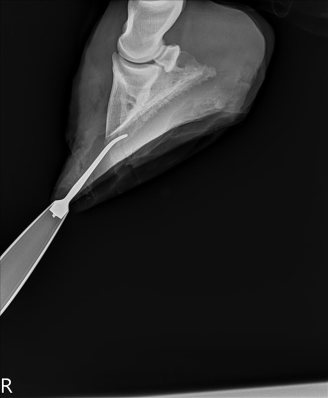

We went out for lunch and then after lunch I sat in his stall with him. He was clearly bored and a bit frustrated, standing and staring into the middle distance. The surgeon was running a bit late from morning farm calls, so they started prepping him at about 2:00. They tranq’d him, pulled his shoes, and did some x-rays to confirm everything.

| Getting his pre-surgery x-rays. |